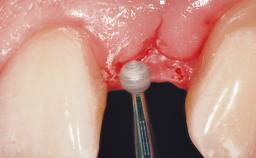

The crown of tooth 21 was splinted to the adjacent teeth with composite resin, and the gingiva was inflamed.